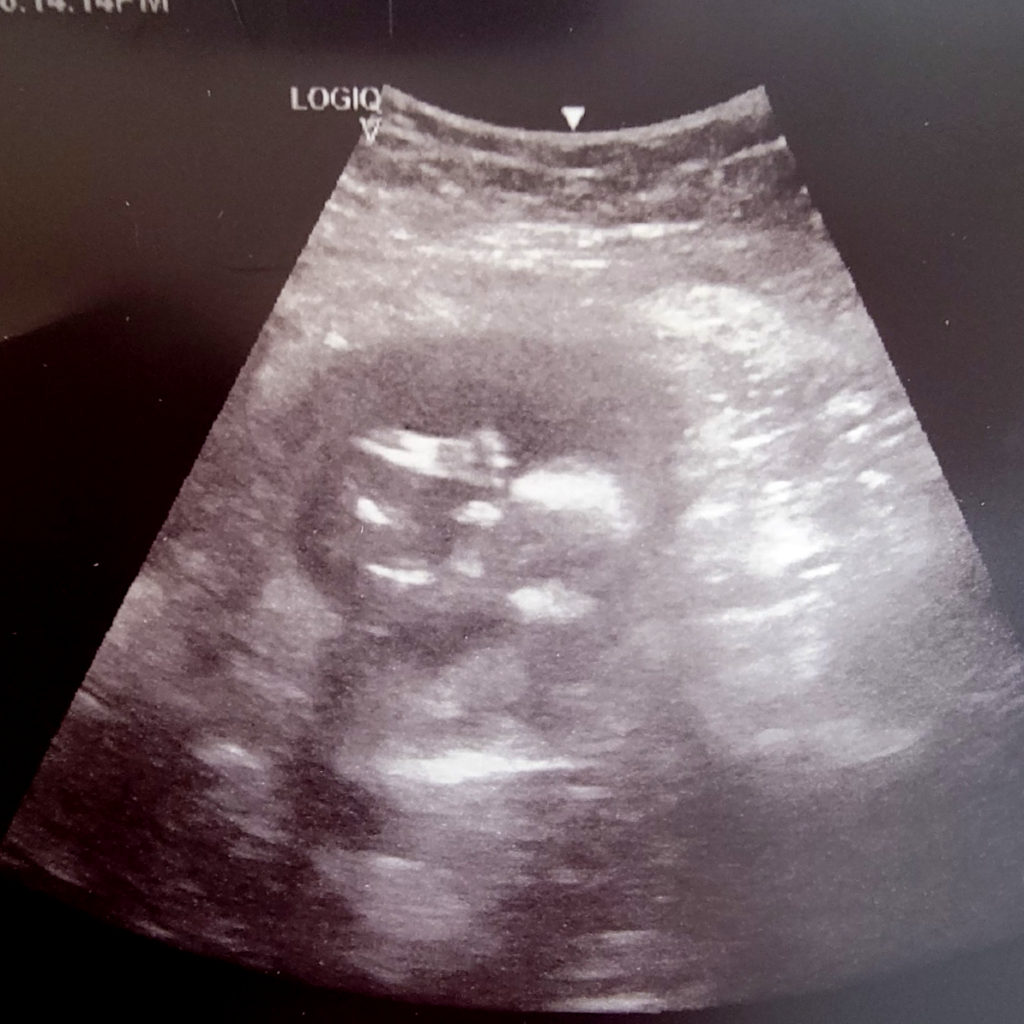

Fourteen weeks! Look at the long feet – Michael had long feet too when he was born, and he is 6’3″ today. Brittany is going through it with morning sickness, but otherwise Mom and Baby are doing well!